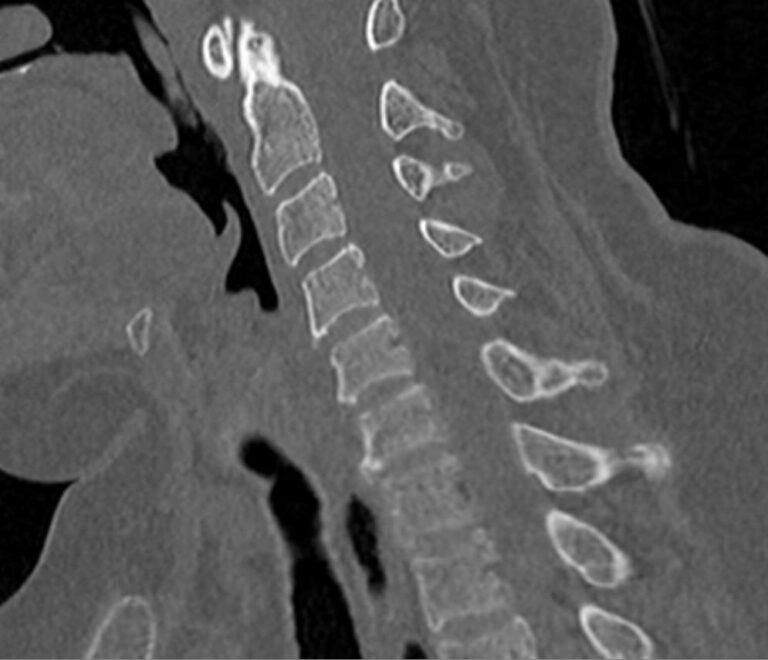

Мультиспиральная компьютерная томография является одним из наиболее информативных методов диагностики дегенеративно-дистрофических заболеваний, травматических, воспалительных изменений, а также опухолевых процессов позвоночника. Методика предусматривает использование рентгеновского излучения для получения детализированных снимков костных структур позвоночника, межпозвонковых суставов и межпозвоночных дисков.

При подозрении на распространенный процесс с поражением различных уровней позвоночного столба показано проведение мультиспиральной КТ трех отделов позвоночника.

В клинике «Доступная медицина» установлены современные мультиспиральные компьютерные томографы экспертного класса TOSHIBA AQUILION в различных модификациях (64-срезовый и 128-срезовый), на которых выполняются комплексные обследования позвоночника, включая одномоментное исследование несколько отделов. Аппараты производят сканирование с помощью рентгеновских лучей, делая тончайшие срезы с шагом от 0,5 мм, затем с помощью компьютерных программ полученные данные преобразуются в изображения трехмерного формата, что обеспечивает точность и достоверность диагностики.